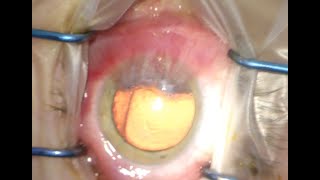

Dr Cronin provides these videos as an educational resource for training ophthalmologists, other ophthalmologists and patients. Dr Cronin specialises in corneal and anterior segment diseases including LASIK, laser eye surgery, cataracts, keratoconus, Fuchs endothelial dystrophy and pterygium surgery.